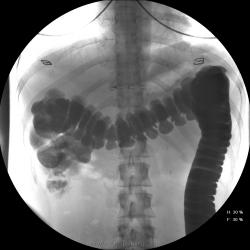

Девушка, 27 лет, жалуется на периодические боли в правой подвздошной области, области паха справа. Во время этого идет нарушение стула - то слабит, то несколько дней не может ходить в туалет, вздутие кишечника. Жалобы несколько лет . Обследованна кем только можно. Хирург посоветовал ирригоскопию. Работа достаточно нервная. До первого случая данных проблем , за неделю, проходила сан лечение в пансионате ( для поднятия общего иммунитета - так говорит), был курс клизм с травами - сама думает, что это не связанно.

В целом -не вижу, к чему придраться, хоть и тонус низковат. Что это? В проекции левого мечеточника. Причем цепочка тенюшек тянется под диафрагму занчительно выше проеции почки?

Цепочка тенюшек - это наша "гордость)" следы от контраста после гистеросальпингоскопии. чтоб вымыть ,надо разбирать стол , а это только с представителем сименса. вот так.) а правые отделы толстой кишки на расширены? я кроме лополнительной петли сигмы сам ничего не вижу. несколько настораживает некоторое расширение правых отделов кишки- может за счет запоров, которые случаются у девушки? не хочется что то пропустить.

При таких симптомах ищи "бабьи дела", может быть хр. аппедицит. Необходимо определиться с характером и продолжительностью болей. Наиболее вероятнно - недостаточность функции Баугиневой заслонки. При указании или подозрении на эту патологию меняется методика обследования. Ваши снимки расположены хаотично, а не по мере заполнения кишечника. При подзрении на недостаточность функции Баугиневой заслонки, по рекомедации Шнигера, заполняется толстая кишка до печёночного угла, а далше только с помощью глубокой пальпации. Если в этом случае удаётся провести контраст в тонкую кишку или при опорожнеии кишечника контраст попадает в тонкую - пиши недостаточность Баугиневой заслонки.

1.Даже сам Витебский признавал оносительность как клапана Баугиньевой заслонки...

2. У Вашей больной типичный дисбактериоз.....эту проблему Вы не исключали? еще не известно...что это были за клизмы...и какую флору она с ними получила...или какой избавилась...